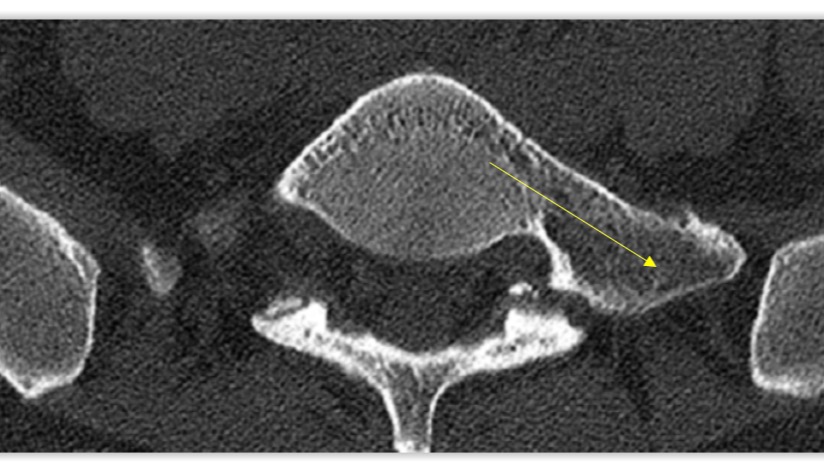

This disorder causes bone-to -bone contact of an “extra bone” at the last vertebrae of the spine with the sacrum, resulting in chronic lower back pain.